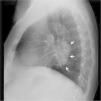

Masa cervical y mediastínica en una mujer de 72 años